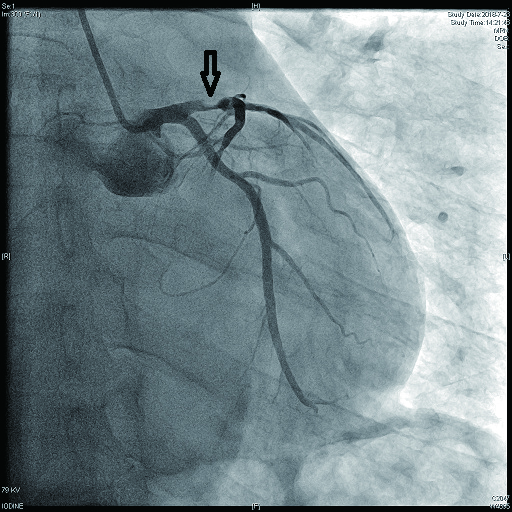

病例1 1 LAD近段(图 9 75%~90% 2级 LAD近段植入支架1枚

病例2 3(图 6~8 LAD近段 次全闭塞 2级 LAD近段植入支架1枚

病例3 1 LAD中段 闭塞 0级 LAD中段植入支架1枚

病例4 3 LAD中段及D1(图 11 LAD 85%及D1闭塞 0级 LAD中段植入支架1枚

病例5 1 LAD中段 闭塞 0级 LAD中段植入支架1枚

病例6 1 LAD中段(图 10 闭塞 0级 LAD中段植入支架1枚

病例7 1 LAD近段 次全闭塞 2级 LAD近段植入支架1枚

图 6 病例2冠脉造影示LAD中段病变

图 7 病例2冠脉造影示LCX病变

图 8 病例2冠脉造影示RCA病变

图 9 病例1冠脉造影示LAD近段病变

图 10 病例6冠脉造影示LAD中段闭塞

图 11 病例4冠脉造影示LAD狭窄,D1闭塞